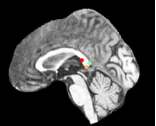

Datasets: A set of isotropic mm MR scans were obtained from the ADNI database [10] to evaluate the proposed method. While, a subset of and images are used for training and testing. All brain images were skull stripped and affinely aligned to the MNI space, thus allowing ground truth planes to be extracted in the standard directions. For cardiac images, we use short-axis cardiac MR of resolution mm obtained from the UK Digital Heart Project [8]. A subset of and images are used for training and testing. ACPC planes are evaluated using the AC and PC landmarks for the distance error calculation. Similarly, we use the outer aspect, inferior tip and inner aspect points of splenium of corpus callosum for mid-sagittal planes. For cardiac MRI, we use six landmarks projected on the 4-chamber plane; the two right ventricle (RV) insertion points, right and left ventricles (LV) lateral wall turning points, apex, and the center of the mitral valve, See Fig. 2.